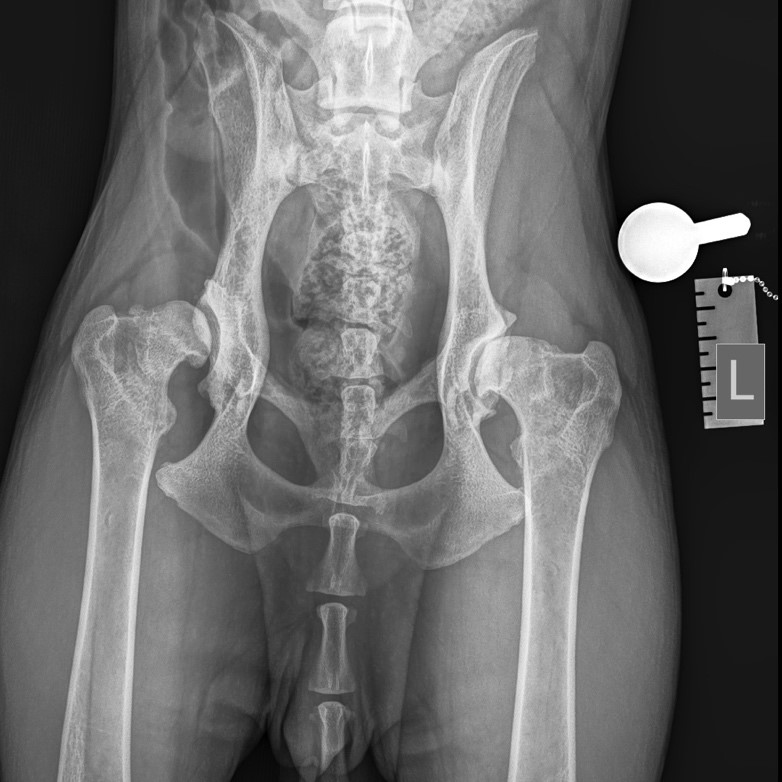

Остеоартрит, часто возникающий на фоне дисплазии тазобедренных суставов (фото 1) - это наиболее распространенная причина хромоты у собак всех возрастных групп. Для лечения собак с клиническими признаками хромоты, а также при первичных (нестабильность) или вторичных (остеоартрит) признаках дисплазии тазобедренных суставов применяются как консервативные методы терапии, так и хирургические вмешательства. К числу хирургических техник относятся тройная остеотомия таза, тотальное эндопротезирование тазобедренного сустава, остэктомия головки и шейки бедренной кости (фото 2). Последняя методика (по опубликованным данным) приводит к неудовлетворительным результатам по объективным и субъективным критериям примерно у 42% собак и кошек3.Предоперационное планирование

На основании неврологического осмотра не было выявлено патологических изменений. По результатам ортопедического осмотра правого и левого тазобедренных суставов: ограничение диапазона движений, крепитация, болезненность при манипуляциях; другие суставы без особенностей.Была проведена рентгенография тазобедренных суставов в дорсовентральной проекции с экстензией тазовых конечностей (фото 1).

Выявлены следующие патологические изменения правого и левого тазобедренных суставов:

- изменение формы головки бедренной кости;

- образование остеофитов на шейке бедренной кости;

- утолщение капсулы сустава (линия Моргана);

- покрытие головки менее 50%;

- сглаживание дорсального края вертлужной впадины;

- субхондральный склероз.